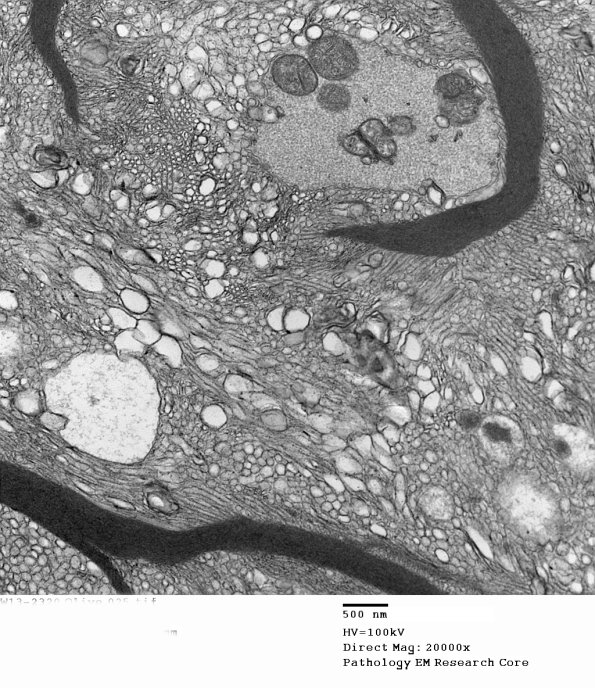

Higher magnification of image #19D1. (electron micrograph)